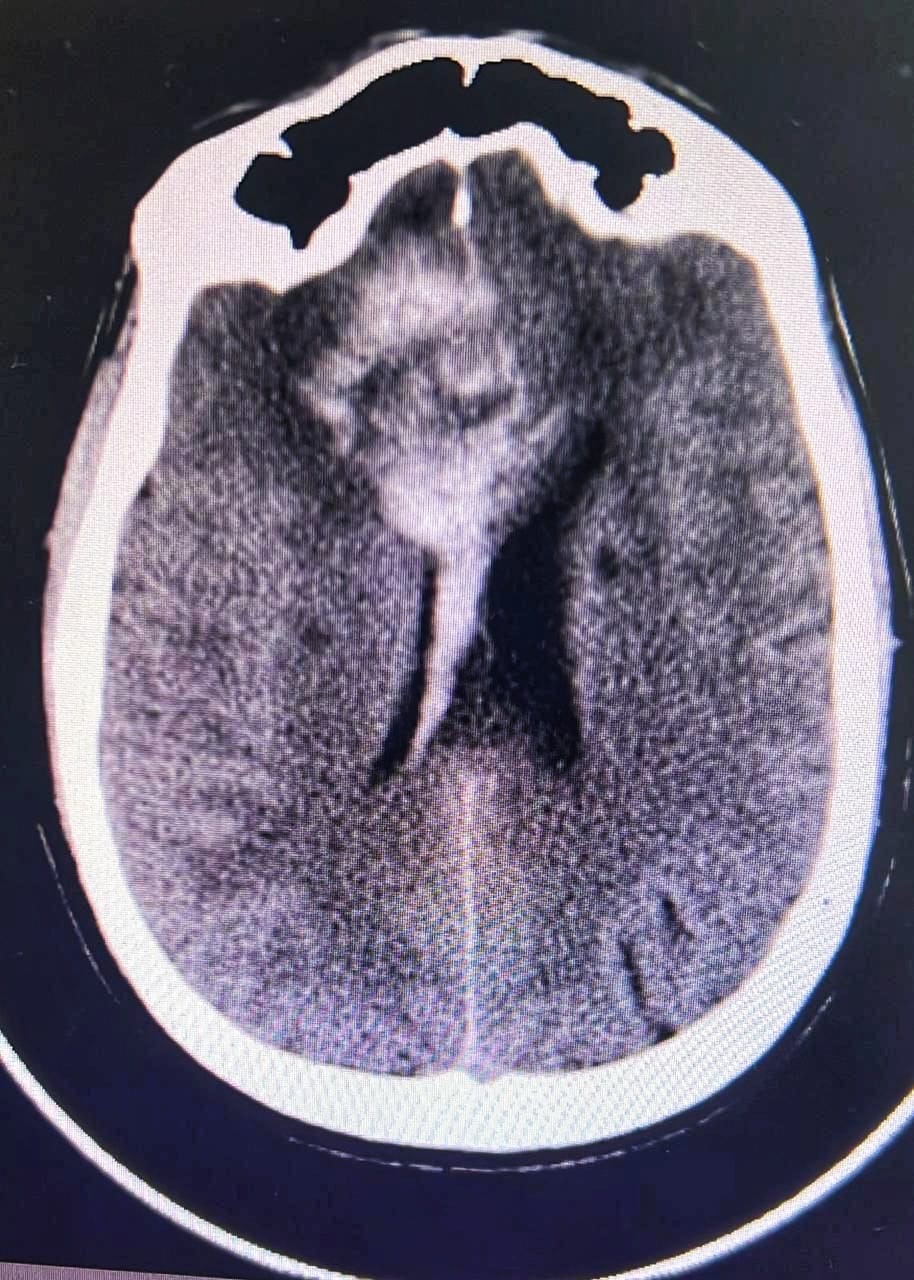

وتم اجراء الفحوصات اللازمة له وتبين وجود تمدد في الأوعية الدموية في الفص الأيسر من الدماغ مسببا انفجار الشريان الوسطي الدماغي الأيسر .

وأوضح الدكتور أنور الهاشم رئيس قسم جراحة المخ والأعصاب والعمود الفقري ان الفحوصات أظهرت تلفا في مركز الحركة في الفص الأيسر ونقصا في التروية الدموية مهددا بفقدان وظائف هذا الفص بشكل شبه دائم .